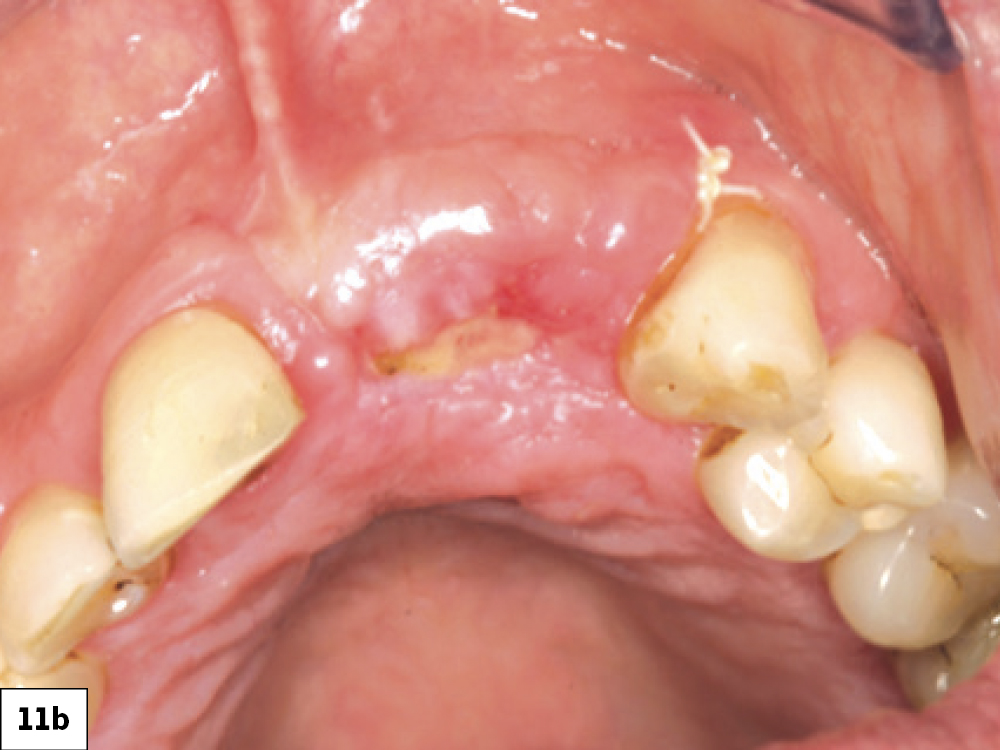

In most ILO cases, the correct treatment is to allow the surgical wound to heal via secondary intention. Allowing the site to heal by secondary intention requires considerable discipline and patient cooperation for a successful outcome (Box 2, Fig. 11). This treatment approach is influenced by various factors such as the health of existing tissue, tissue thickness, location, patient age and the size of the dehiscence. The technique involves implementing the following:

Successful healing by secondary intention: (a) two-week postop with ILO, (b) three-week post-op, (c) successful re-epithelization at four-week post-op.

Figures 11a–11c: Successful healing by secondary intention: (a) two-week post-op with ILO, (b) three-week post-op, (c) successful re-epithelization at four-week post-op.